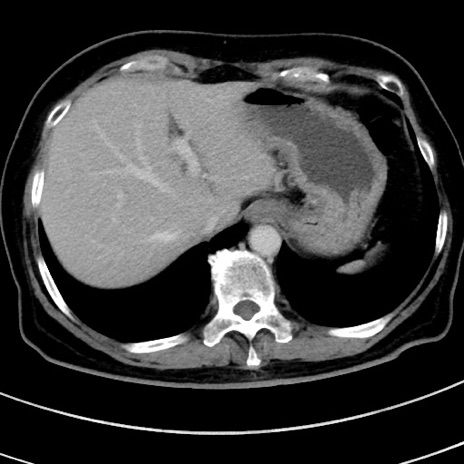

症例9(横断像)

【症例】 60歳代女性

【主訴】むかつき、みぞおちの痛み

【現病歴】3日前よりむかつきがあり、食事がとれない。

【既往歴】糖尿病

【身体所見】発熱なし、心窩部圧痛軽度あるも、腹膜刺激症状なし。

【データ】WBC 7400、CRP 1.92